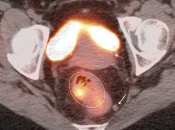

Presentation of Primary Cancer:

- Focal bowel uptake, usually with associated bowel wall thickening.

- If long-segment, think inflammation.

- Normal physiologic bowel uptake (discussed here) can be very focal and isolated to only one part of the colon, most commonly the cecum and rectum. Always look for associated bowel wall thickening on the CT images.

- Hemorrhoids are often intensely avid in the ano-rectal region (and are usually not visible on the CT images). Be certain that uptake does not lie more superiorly in the rectum. Additionally, carefully assess for an accompanying soft tissue density to exclude an anal cancer.

- Beware the small rectal cancer! As the ano-rectal region frequently demonstrates intense physiologic uptake, it is very easy to overlook a rectal malignancy, especially if it is an incidental finding. To avoid this error, always evaluate the rectum carefully on the sagittal whole body images. It is shocking to see how readily apparent a rectal cancer can be on these images, yet so easily overlooked in the axial plane.